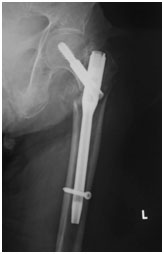

A.転子部骨折:ガンマネイル固定

手術後は、翌日からリハビリを開始 します。手術2日目には車いすでの移動を始めます。骨折の不安定性にもよりますが、早期に荷重をかけながら歩行訓練を行います。